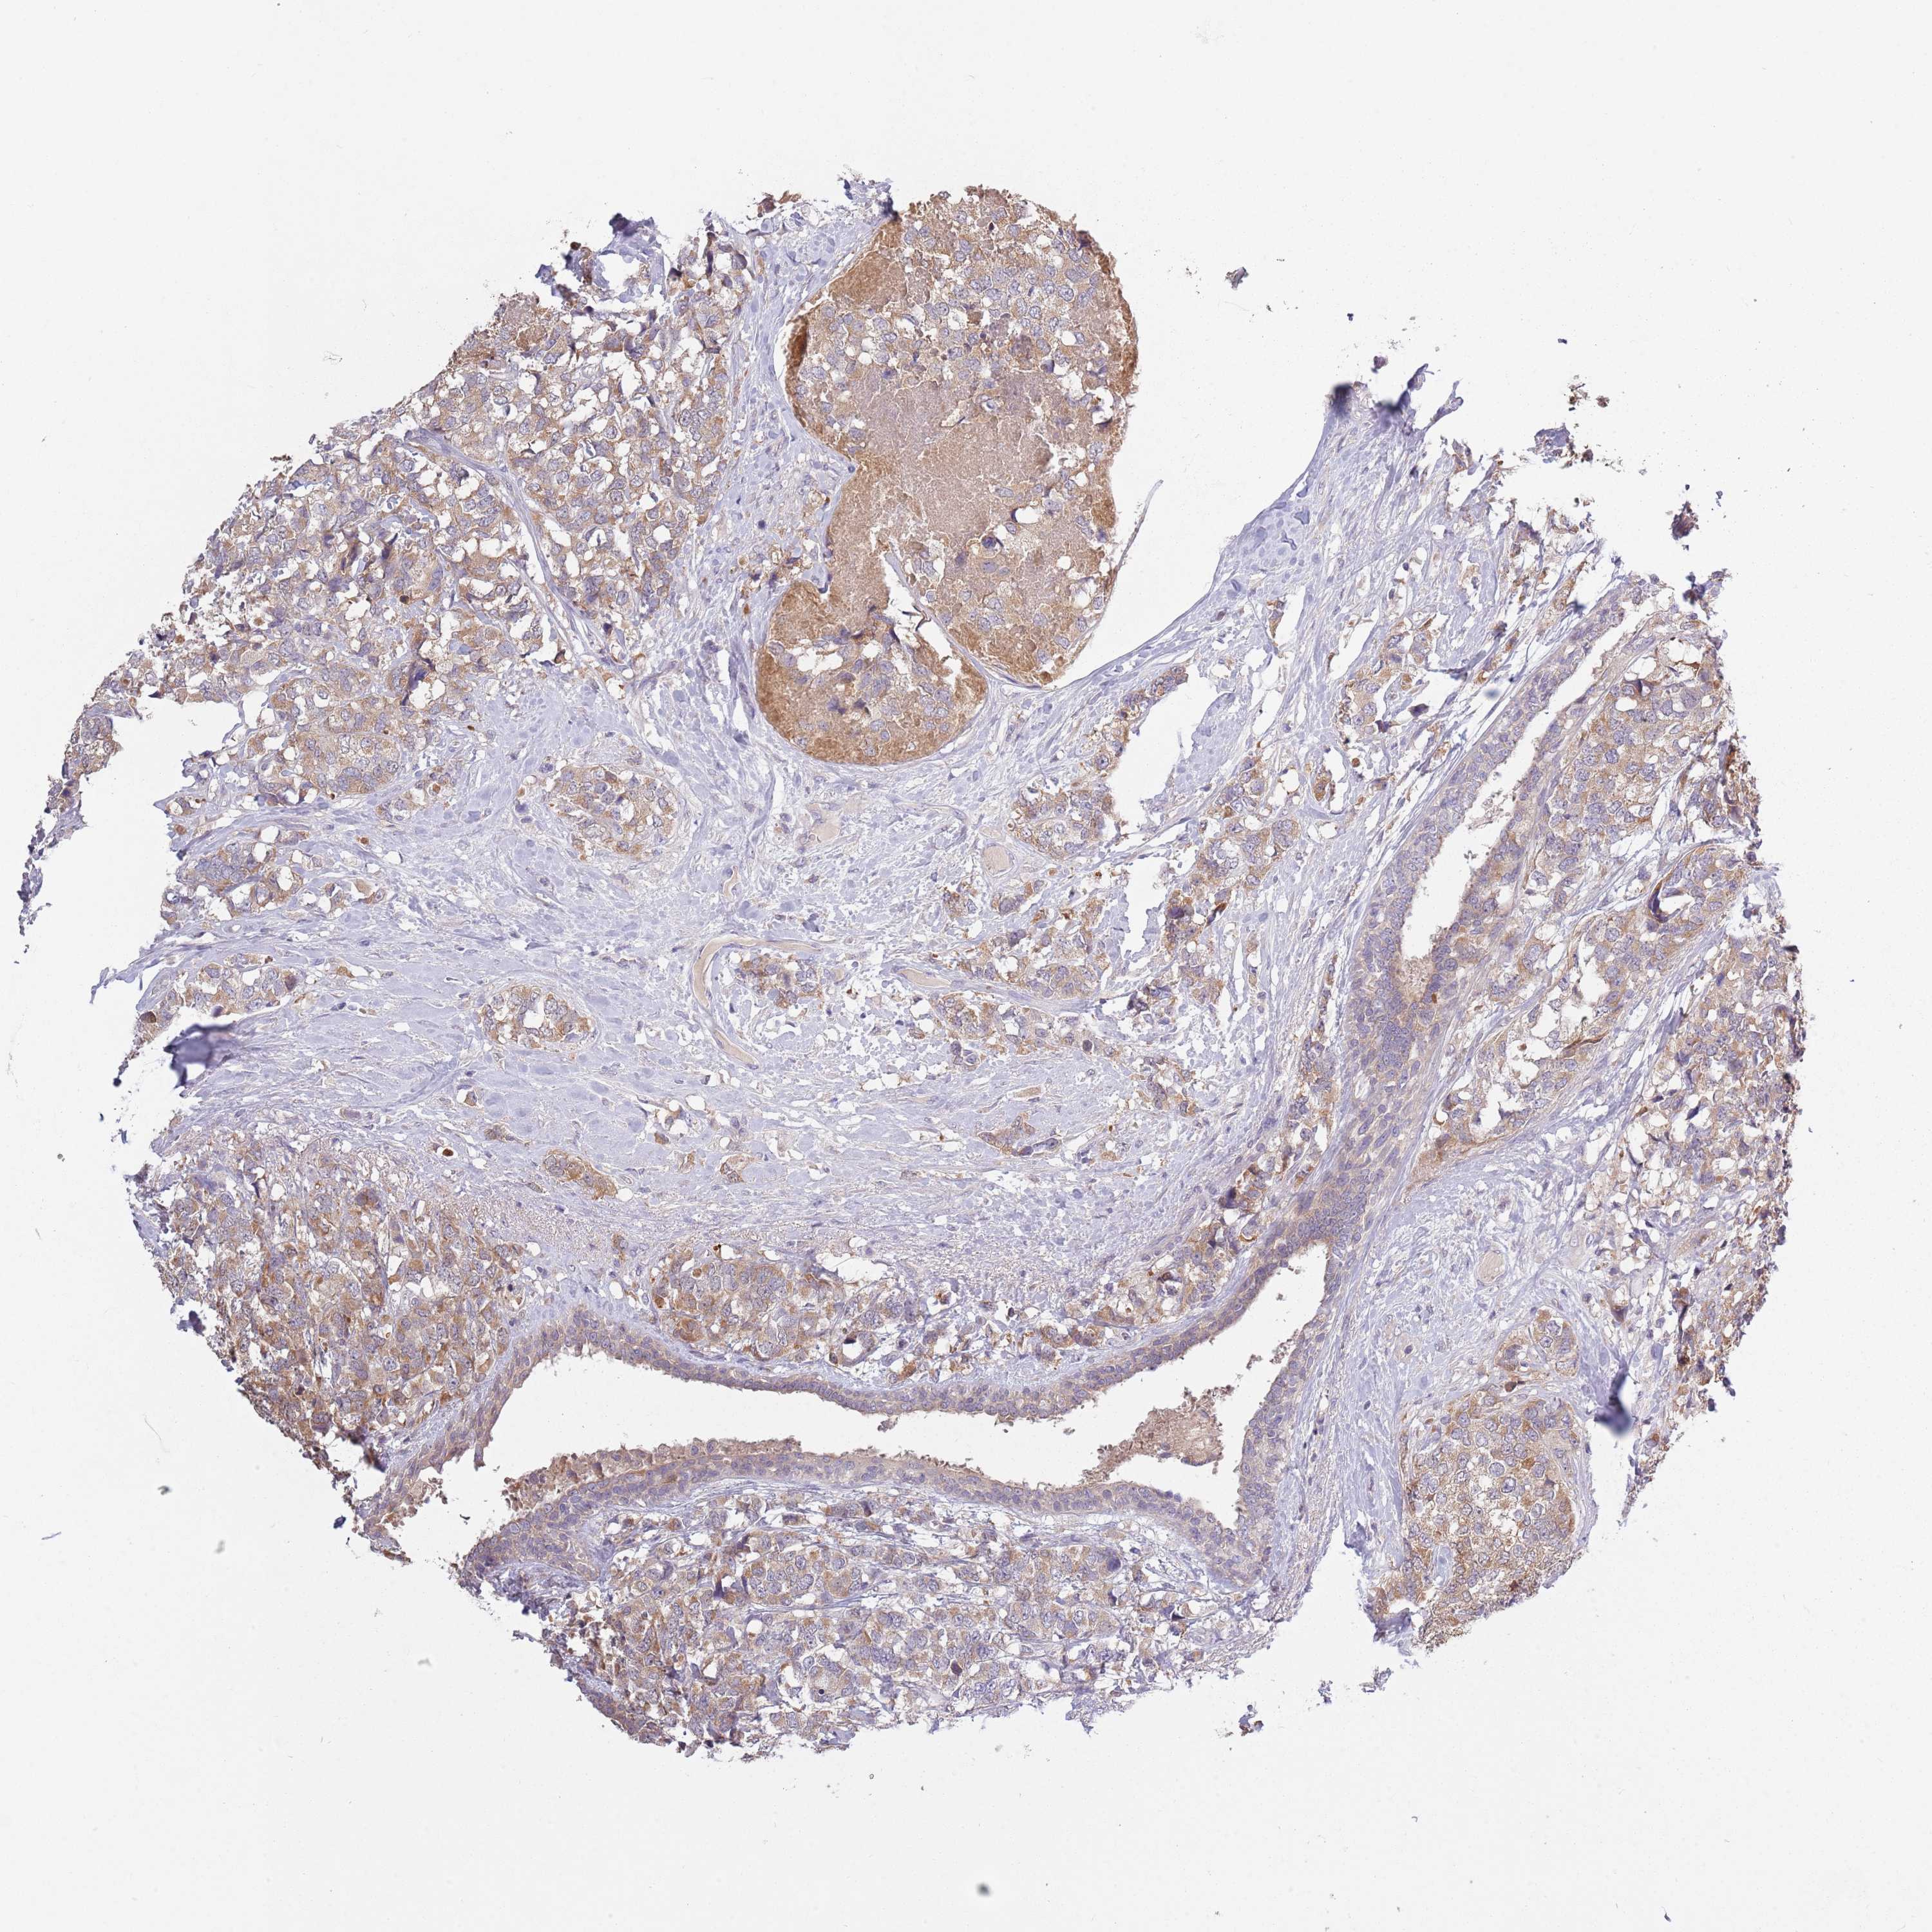

BRCA TCGA BRCA VALIDATION PROTEIN EXPRESSION